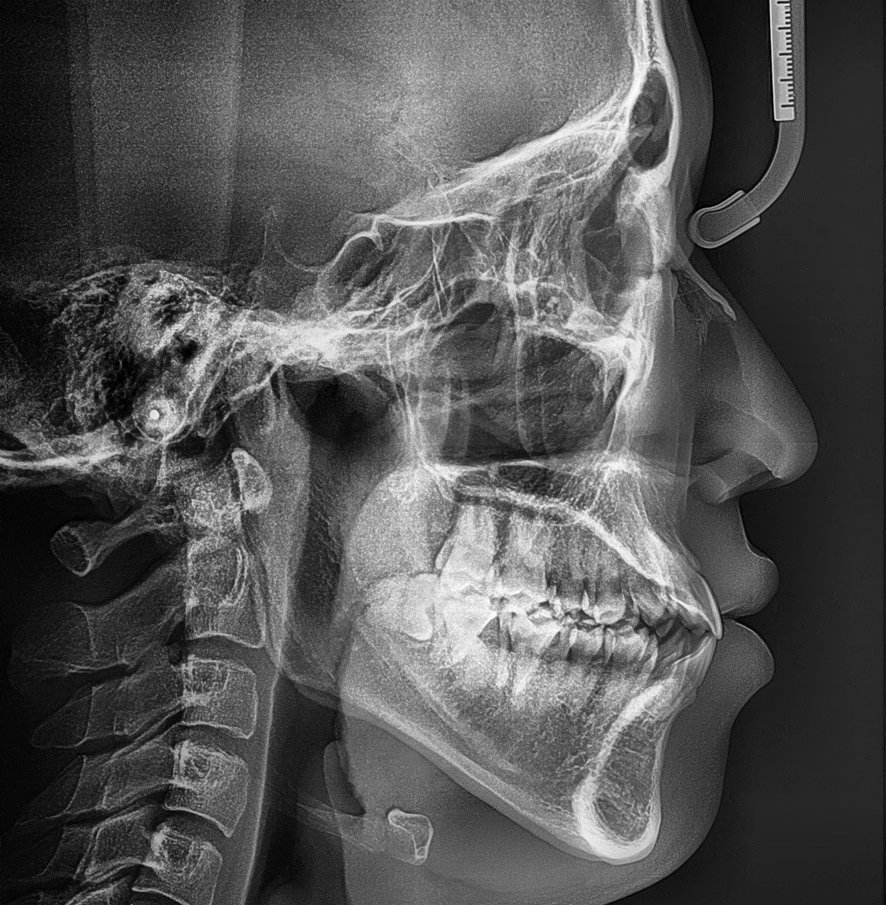

투디치과 최대리님 교정중

이 사진은 교정 시작하신지 13개월째인 현재 모습이에요. 자세히 보시면 앞니쪽 치아가 들어가서 입술도 다물어져 보여요. (오 싱기방기+.+!!)

사진으로 잘 모르시겠으면 볼펜같은거로 코와 턱끝을 일직선으로 대보시면 확실히 많이 들어간 것을 확인하실 수 있어요.

위 사진은 코끝과 턱끝에 볼펜을 댔을 때 입술이 나와서 닿지만 아래 사진은 입술이 볼펜에 닿지 않죠^^?

아직 마무리가 되지 않은 중간단계이지만 안모의 변화를 조금씩 느끼실 수 있어요.

미세하게 변한 것 같지만 13개월동안 많은 변화가 일어났어요. (3-4mm정도는 앞니가 들어가신것 같아요.)

우리 얼굴엔 1mm차이도 큰 변화를 준답니다.